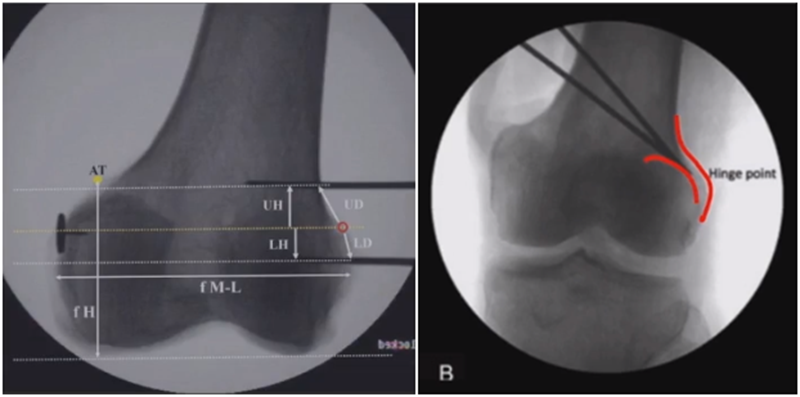

3、选择合页位置和截骨线

合页点的选择与HTO一样,通常需要尽可能接近畸形部位,既要有很好的骨质结构,还要有坚韧的软组织覆盖,以保证稳定性和术后有良好的血运。合页宽度不宜太长,通常保留在5mm。

合页点定位有两种方法,一种为定位在股骨外后髁上缘2mm位置,通常将此区域叫做“鹰嘴区”,以此为解剖标记法来定位合页点。

另一种通过导针从截骨入点向股骨外后髁后缘打出一条切线,此切线与外侧骨皮质的交点,也可作为合页点,这种方法称为导针法。这两种方法在手术之中是可以互为验证的。

截骨线入点同样也可以采用两种方法选择。一种为钢板标记法,即使用tomfix钢板远近端的无孔区作为截骨入点。

另一种为解剖标记法,在切开显露后可以看到一处恒定血管,即内侧上横动脉,在此附近做截骨即可。如做外侧闭合楔时,同样在外侧也可以看到一处恒定血管,为外侧横动脉。

合页点和截骨线已确定好,按照术前计划打入导针,测量截骨深度。